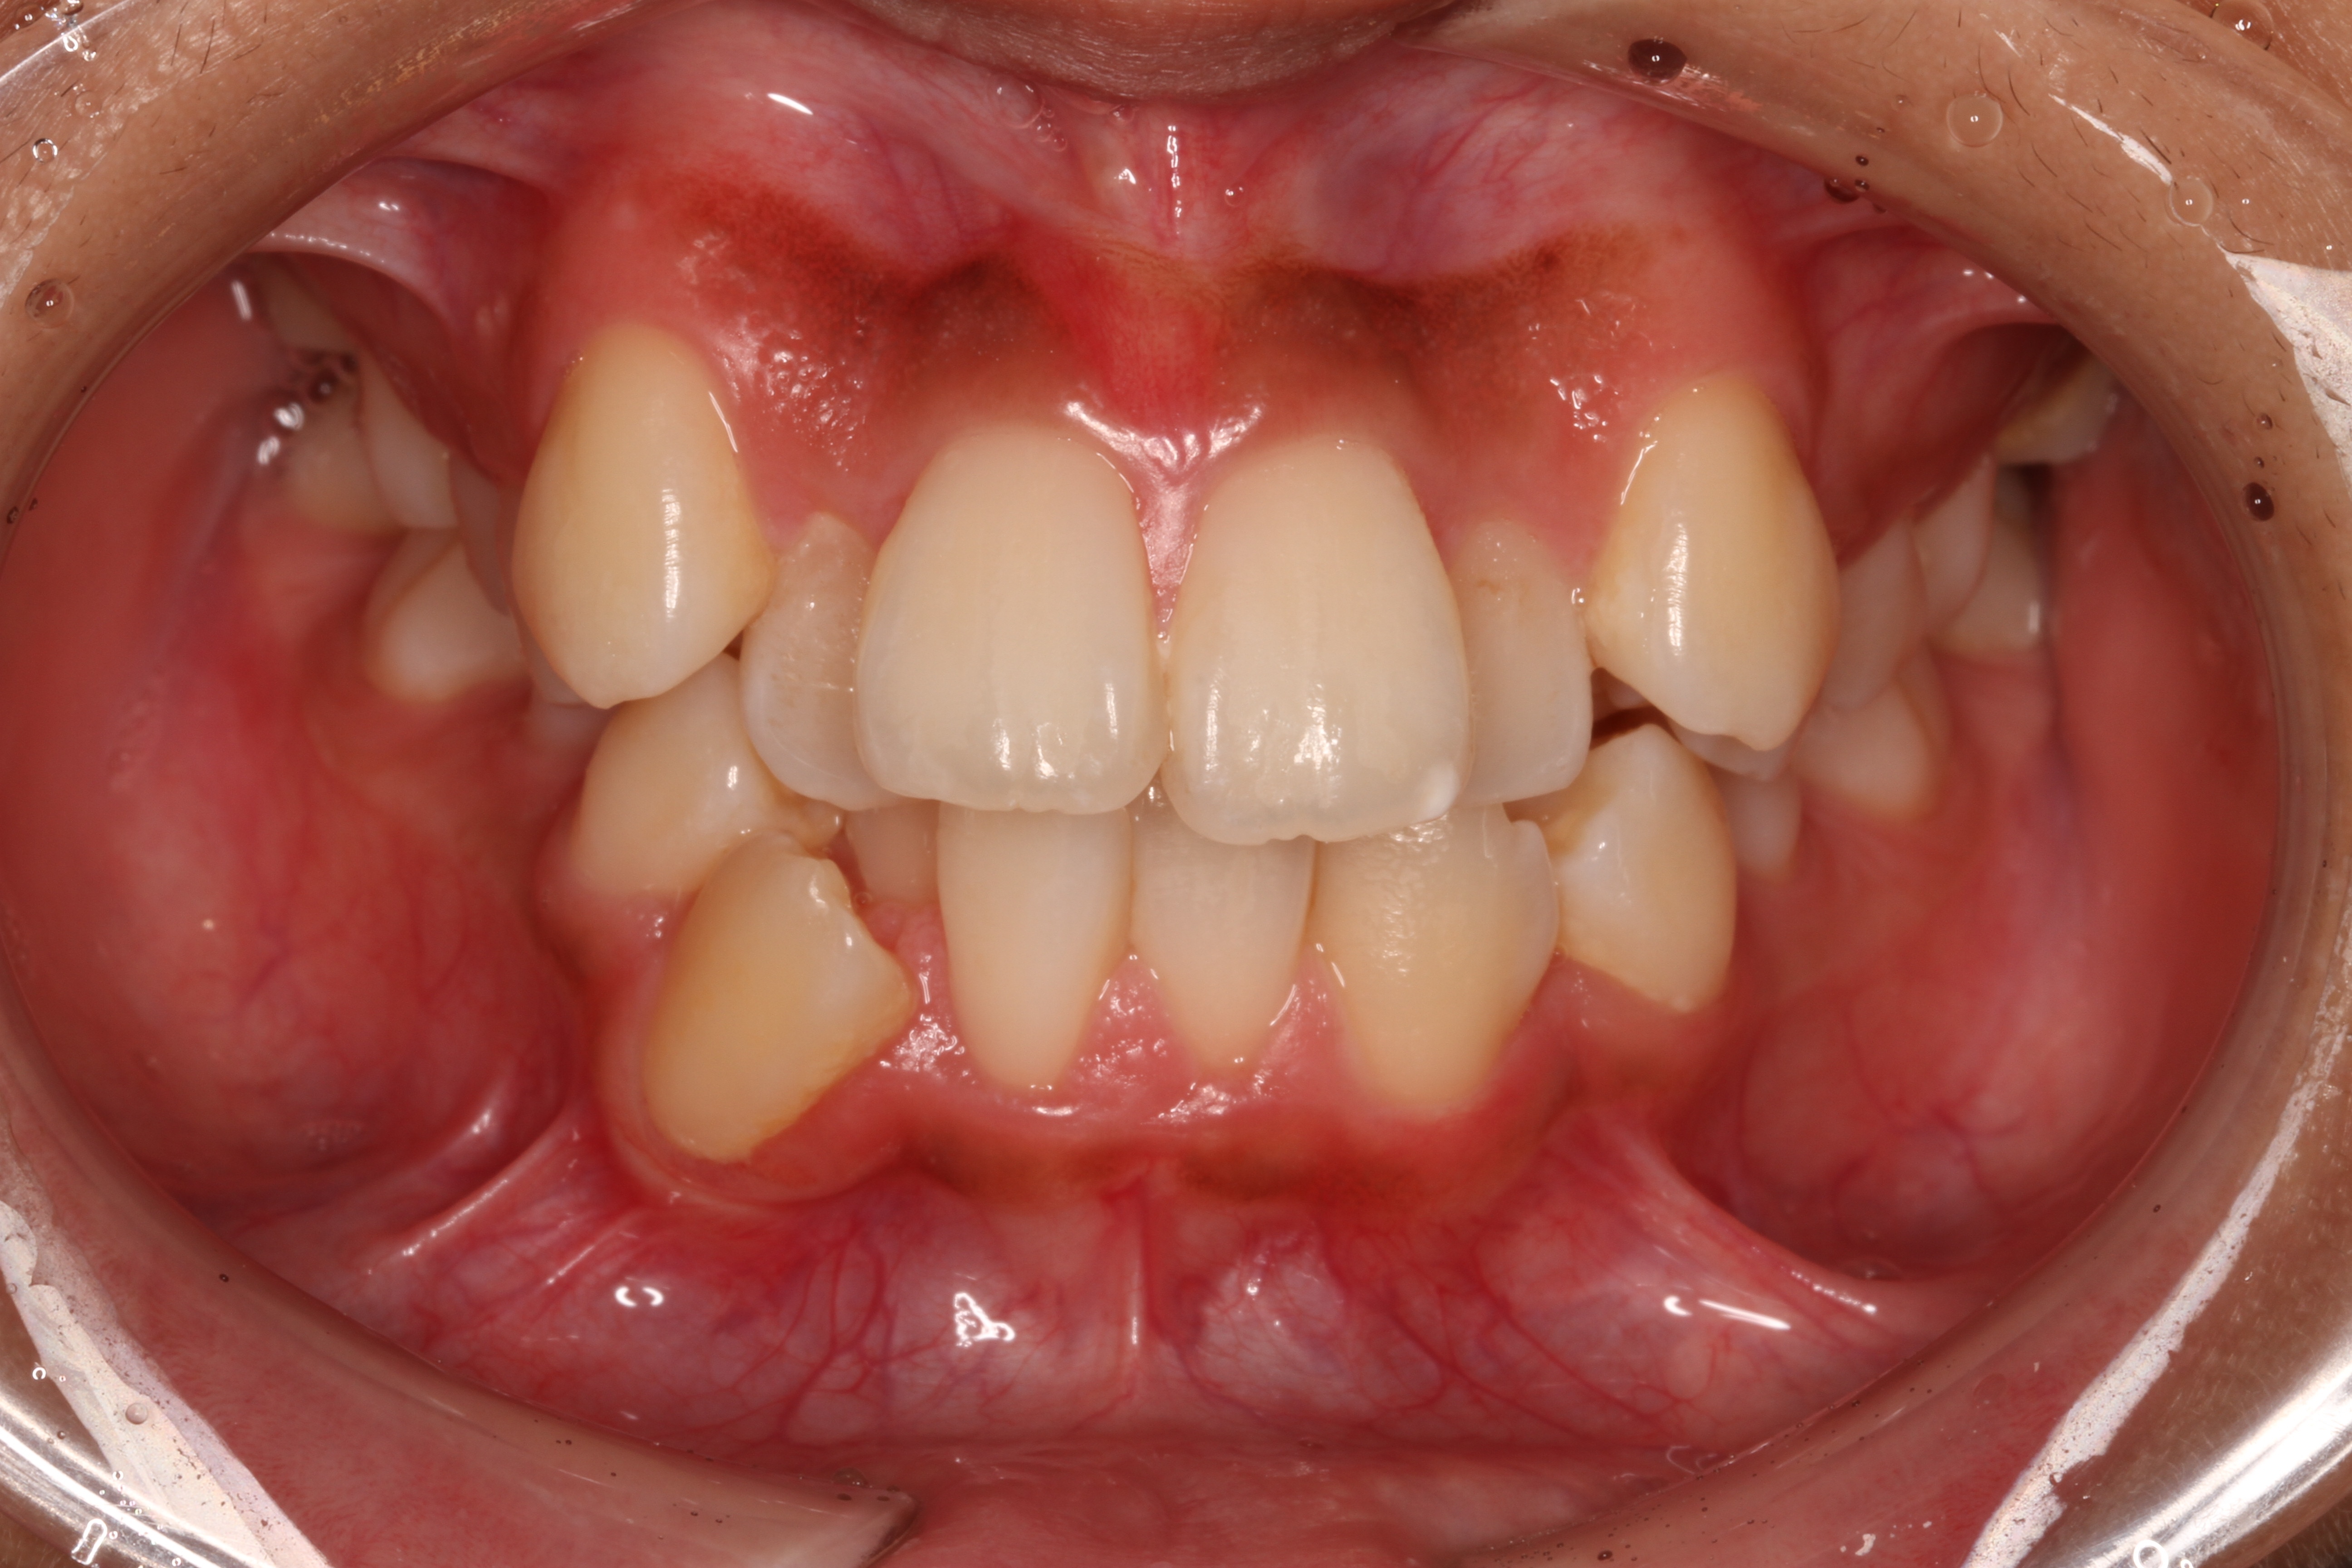

- 患者様情報30代 女性

- 来院動機歯並びが気になる

- 治療内容矯正治療

- 治療期間1年5ヶ月

- 治療費用1,063,700円(税込)

検査費、治療費、月々の調整費込 - 治療のリスク歯肉退縮の可能性がある、装置装着の痛みを感じる場合がある